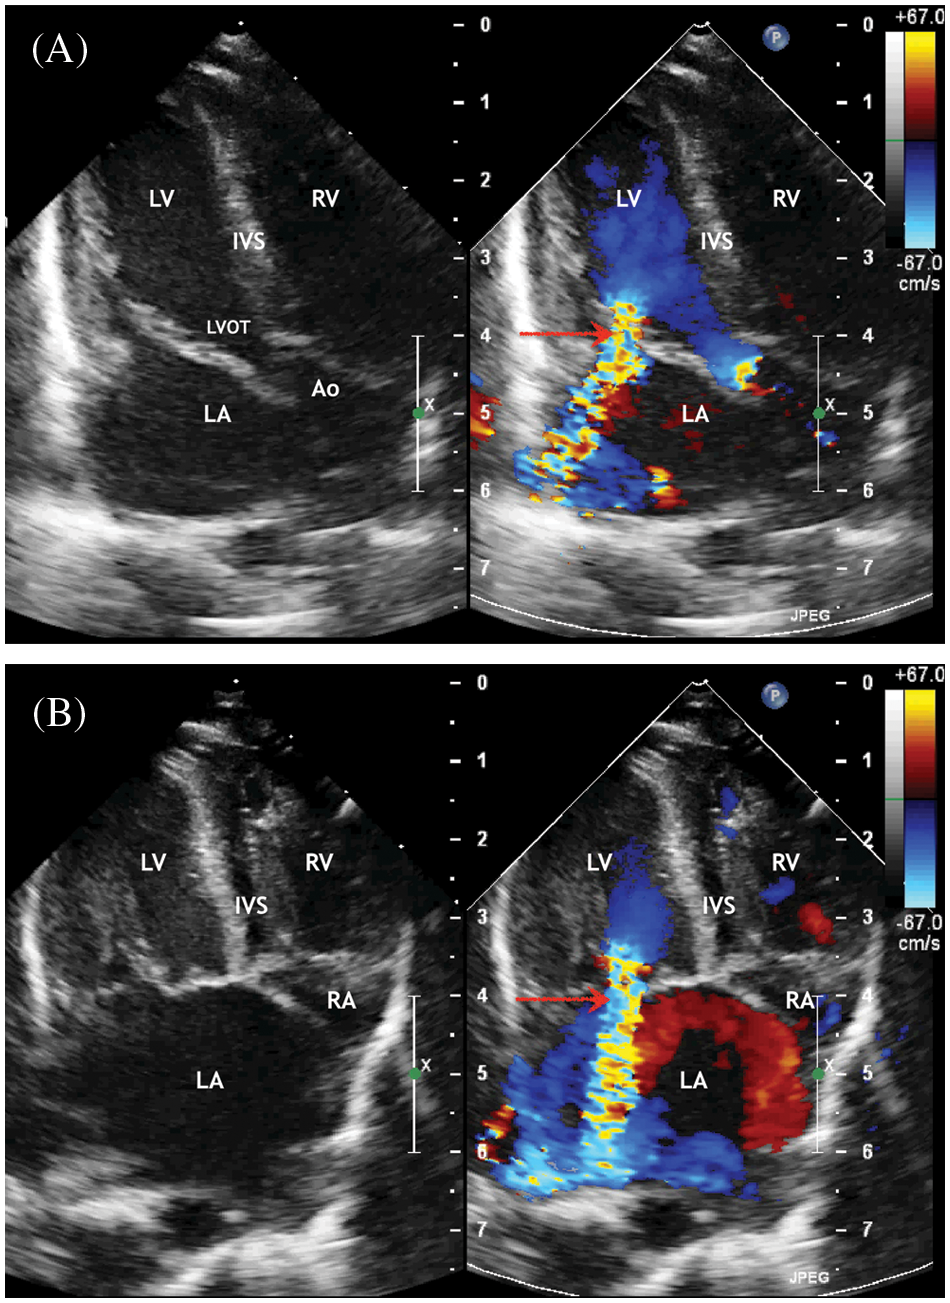

Figure 2: ECHO. (A) Five chambers view. Systole phase of the LV. Severe mitral regurgitation (marked with an arrow) with enlarged of the left atrium. (B) Four chambers view. Systole phase of the LV. Severe mitral regurgitation (marked with an arrow) with enlarged of the left atrium. Displacement of the interatrial septum to the right

Abbreviation: RV, the right ventricle; LV, the left ventricle; LA, the left atrium; RA, the right atrium; IVS, the interventricular septum; LVOT, the left ventricle output tract; LA, the left atrium; IVS, the interventricular septum; Ao, the ascending aorta.